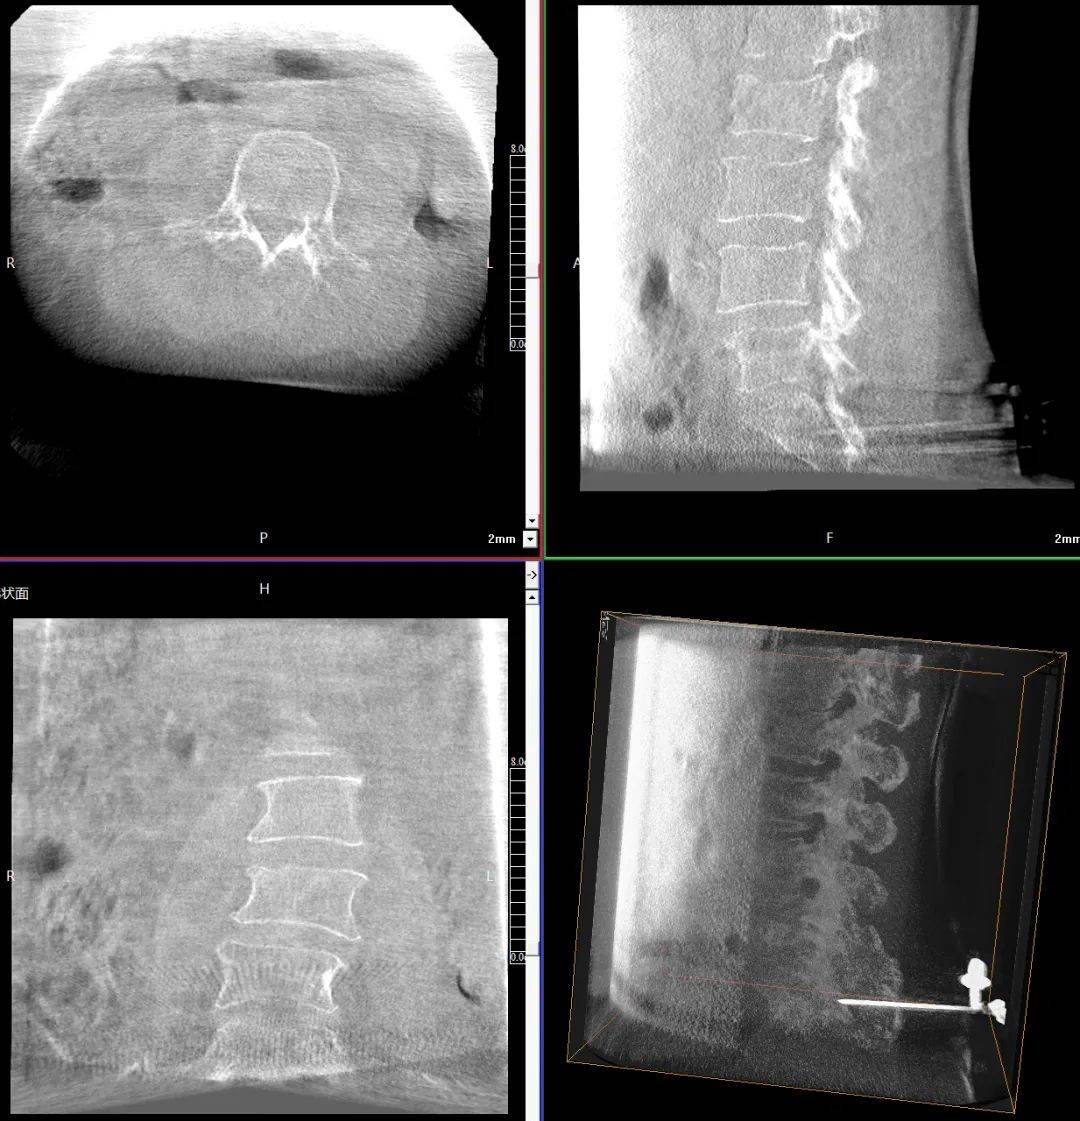

臨床表現(xiàn):患者主訴腰背部劇烈疼痛,活動(dòng)受限;查體證實(shí)腰背部局部壓痛、叩擊痛明顯,尤其在受累椎體區(qū)域;影像學(xué)檢查顯示多節(jié)段椎體壓縮性骨折,椎體高度明顯降低,椎體形態(tài)不規(guī)則,椎體扭曲畸形,椎弓根狹窄。

患者術(shù)前影像